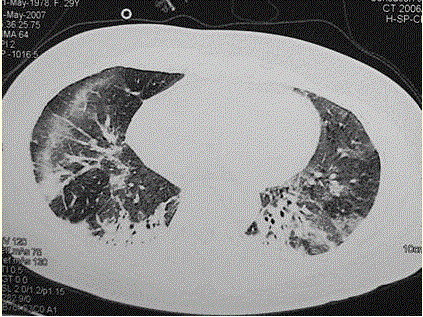

问题  患者女,29岁。间断干咳10年余,加重4个月,伴进行性呼吸困难1个月。病程中出现双手及双足非凹陷性肿胀、双侧膝关节及双侧肘关节对称性肿痛,面部出现细小红色丘疹。体检:T 36.5℃,P 88次/min,R 22次/min,BP 110/75 mmHg,SpO 93%(自然)。额部、前胸及后背散在红色小丘疹,双肺呼吸音增强,双肺中下肺野可闻及爆裂音,右肺明显。胸部CT 如图所示。 应采取的治疗措施包括

选项 A、糖皮质激素+免疫抑制剂 B、雾化吸入糖皮质激素及支气管扩张剂 C、及早插管上机,给予机械通气 D、大剂量抗生素治疗 E、无创通气 F、糖皮质激素治疗 G、吸氧

答案 AFG